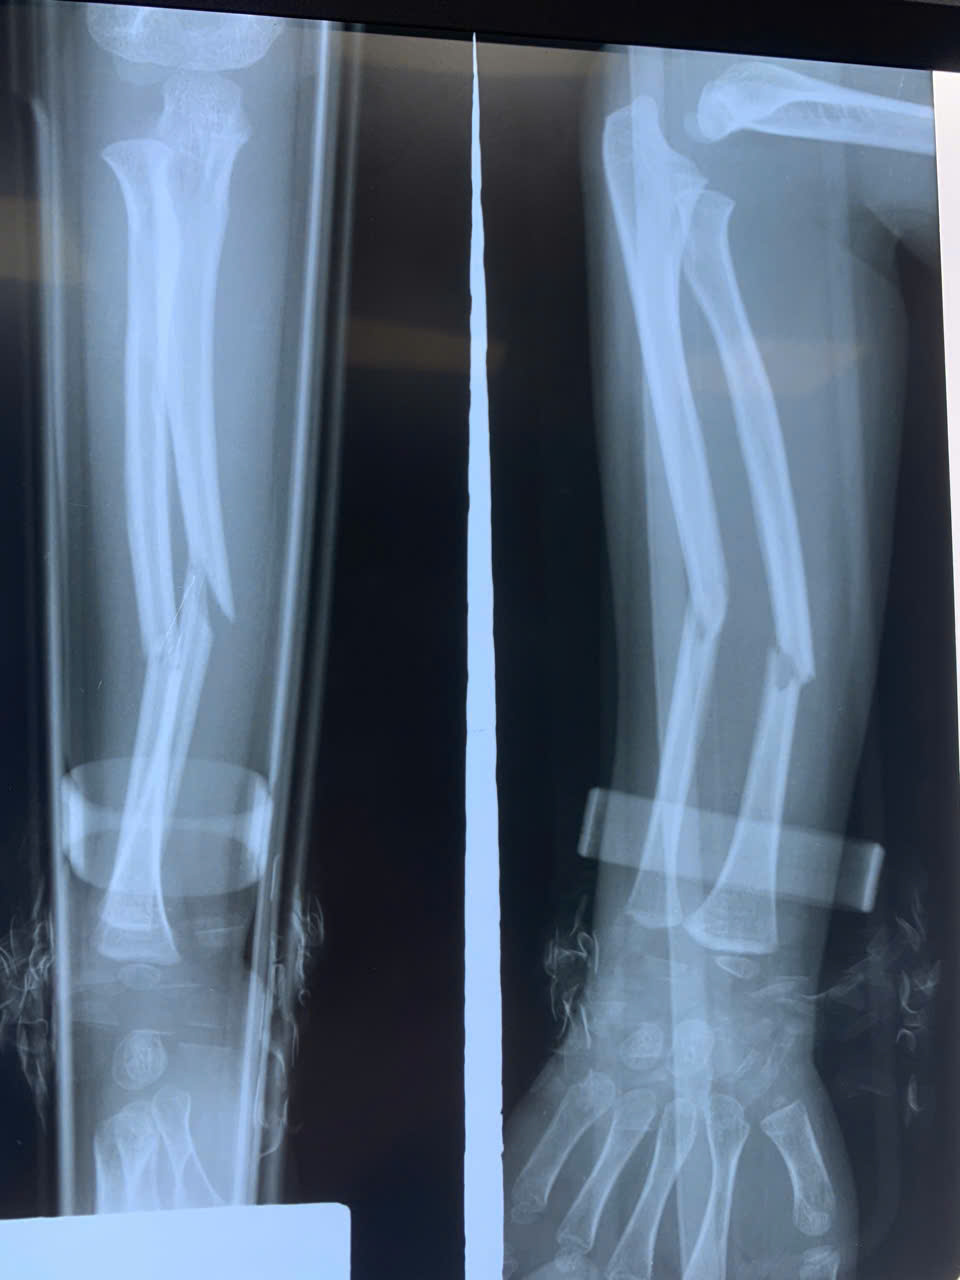

Các vị gãy xương chi thể đã ứng dụng được phương pháp này

như gãy xương cánh tay, cẳng tay, xương đùi, xương cẳng chân, ngón chân, ngón

tay…